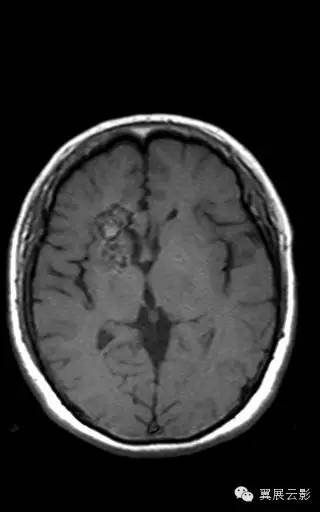

右侧基底节区可见不规则团片状混杂信号灶,累及右侧侧脑室前角,大小约15×34mm,边界尚清,呈爆米花样改变,T1WI等高信号,T2WI/FLAIR呈混杂稍高信号,边缘可见低信号环,无明显占位效应,DWI低信号。